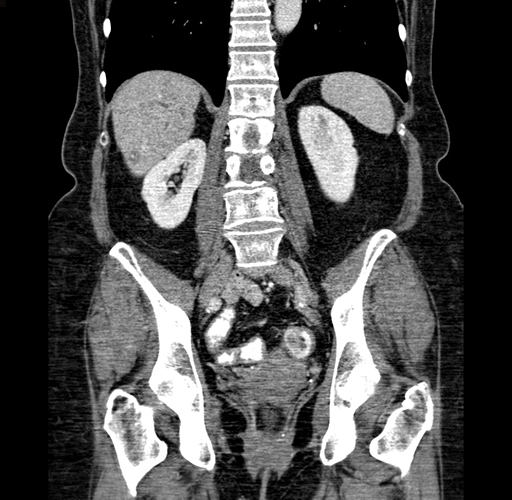

Coronal Venous